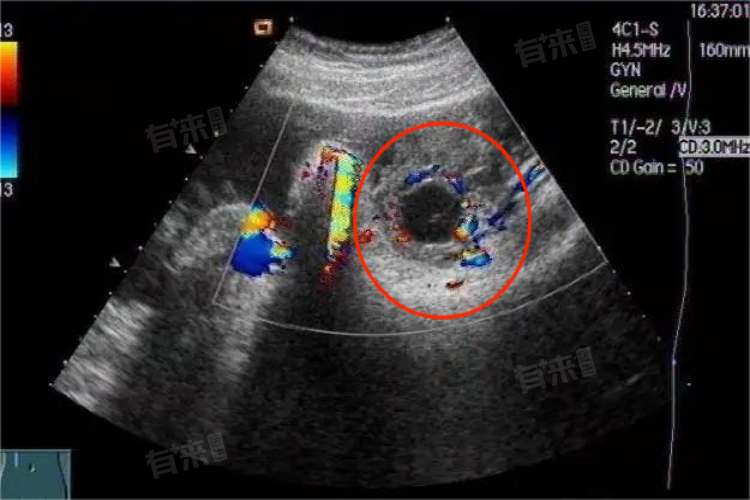

- 当医生在妇科超声检查中考虑黄体时,通常是在分析卵巢的影像学表现,寻找与黄体相关的特定征象。这些征象可能包括卵巢内的一个或多个囊性结构,这些结构在超声图像上呈现出特定的形态和回声特征。这些特征通常与黄体的生理变化相一致,如黄体在排卵后的增大、其内部的血管分布以及可能的囊性变等。

- 妇科超声检查作为一种无创、无痛的检查手段,能够清晰地显示女性生殖系统的结构,包括子宫、卵巢、输卵管等。在检查过程中,医生会使用高频超声波探头,通过腹壁或阴道对女性生殖器官进行扫描,以获取详细的影像学信息。当医生在超声图像中发现与黄体相关的征象时,会结合患者的临床表现、月经周期以及实验室检查等信息,来综合判断这些征象是否与黄体有关。

- 考虑黄体在妇科超声检查中的意义在于,能够帮助医生评估女性的卵巢功能,特别是黄体的形成和功能状况。黄体的正常发育和功能对于女性的生殖健康至关重要。如果黄体功能异常,可能会导致月经不调、不孕、流产等妇科问题。因此,通过妇科超声检查来观察黄体的状况,可以为医生提供重要的诊断线索,有助于制定个性化的治疗方案。